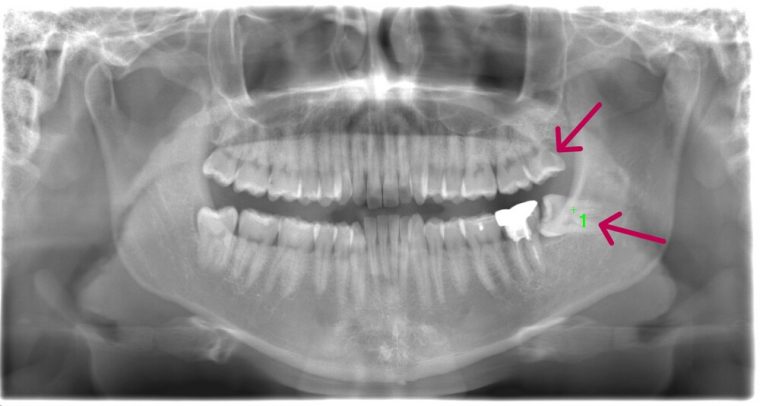

| 治療方針 |

右下の親知らずが斜めにはえていて、頭が半分出ている状態です。このままでは食べものが挟まりやすく、歯ブラシで汚れを落とすことが難しいです。 虫歯や歯周病になりやすくなってしまうため抜歯を行いました。 親知らずが下顎神経と近いため、CTを撮影して確認してから抜歯を行いました。 |

| 特記事項 |

下顎神経が親知らずと近い場合、親知らず抜歯を2回に分ける場合があります。 まず1回目に歯冠だけを抜きます。 手前の歯でストッパーになっている部分を落とすことで、歯根が移動して神経から離れます。 1年程経過をみて、2回目の抜歯を行います。 |